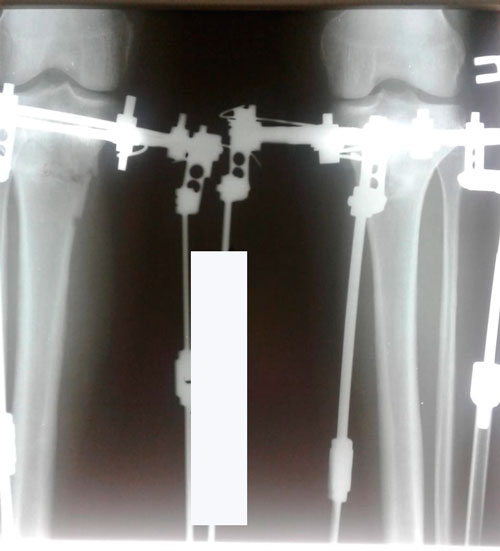

Дата операции 21.03.2018г.

Дата снятия аппаратов 06.07.2018г.

Срок лечения 105 дней.